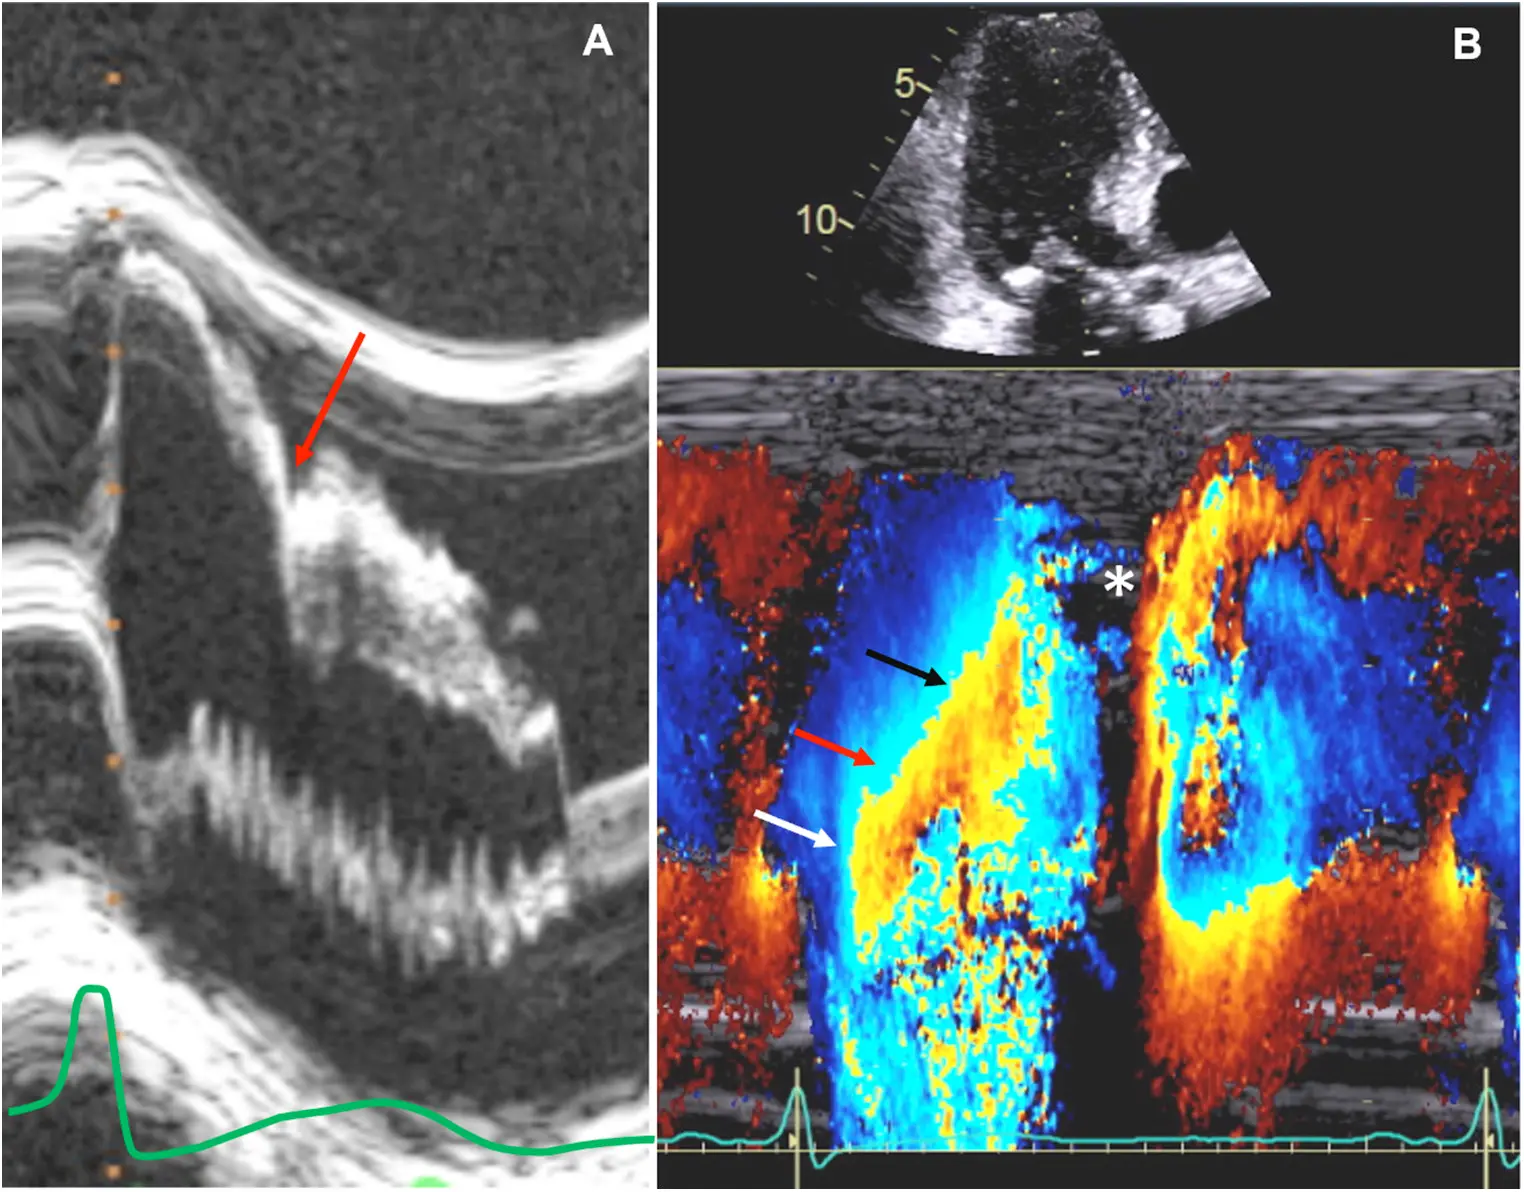

- midventricular obstruction (MVO)

- an important subtype of HCM to recognize as it may result in refractory symptoms and be associated with an increased risk of ventricular arrhythmias, mortality, and LV aneurysm (apical aneurysms often?) with or without thrombus.

- usually related to hyperkinesia of the mid-LV cavity → apposition of hypertrophied mid-septum and hypertrophied papillary muscles

- Color-flow Doppler shows turbulence at mid-ventricular level

- CWD typically shows a narrow, late-peaking systolic velocity (“ice pick” appearance)